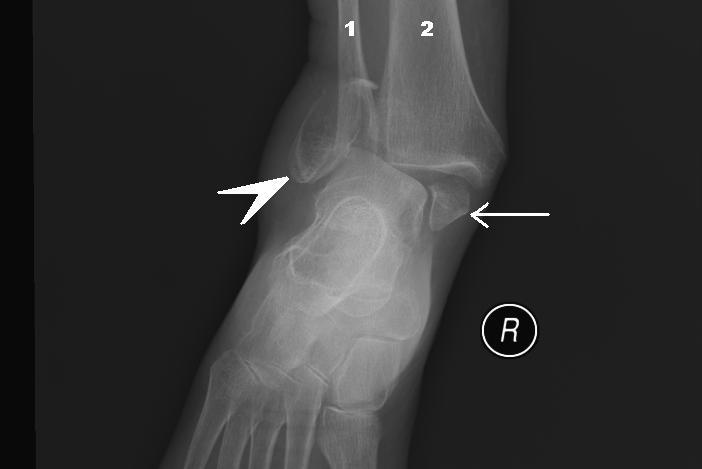

Clinical relevance - Pott’s fracture-dislocation

Can be termed bimalleolar fracture (medial and lateral malleoli).

Can be termed trimalleolar fracture (medial and lateral malleoli and distal tibia).

Produced by forces eversion of the foot. Occurs in a series of stages:

1) Forced eversion pulls of medial ligaments, producing an avulsion fracture of the medial malleolus.

2) Talus moves laterally, breaking off the lateral malleolus.

3) Tibia is forced anteriorly, shearing off the distal and posterior part of the talus.